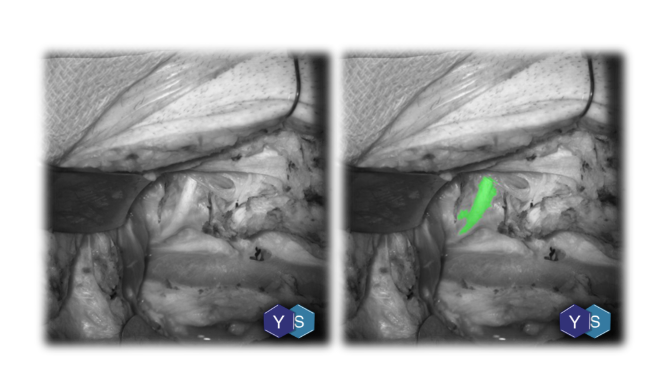

A device that aids surgeons to see and identify nerves in real-time during surgical procedures so that they can "SEE and AVOID" accidental injury and/or PRESERVE and REPAIR nerves.

• Detection of nerve branches as small as 100um

• Real time detection (video frame rate) of intraoperative nerves